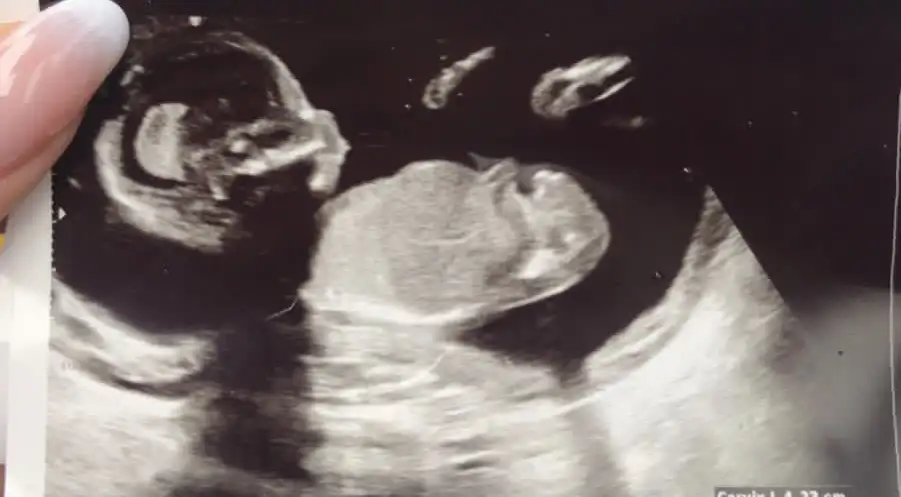

Arkadaşlar selam bizde çok kız bebek istiyorduk 12. Ve 14. Haftalarda doktorumuz kız demişti ama bugun 16.5 haftalık kontrolümüzde yanıldım diyerek erkek olduğunu söyledi ultrason fotoğraflarını paylaşıyorum ne düşünüyosunuz